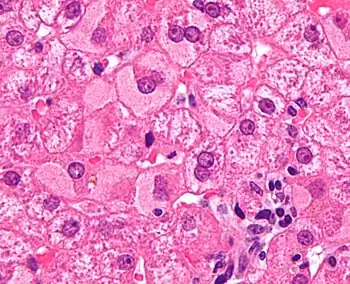

| Micrograph showing ground glass hepatocytes, which are seen in chronic hepatitis B infections (a type of viral hepatitis), and represent accumulations of viral antigen in the endoplasmic reticulum. H&E stain. | |